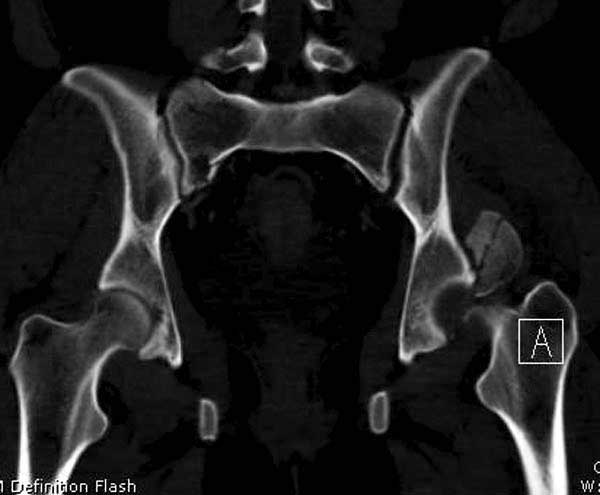

В диагноз еще необходимо внести закрытую (?) ротационно-нестабильную травму таза с переломами лонных седалищных костей, боковой массы крестца справа.

Перелом позвоночника и боковую компрессию таза отнесли к стабильным переломам и не стали форсировать события до лучших времен...

После спадения отека на стопе произведена фиксация тарана. Кстати, коллеги пересмотрели первоначальную консультацию по позвоночнику и на двух уровнях провели фиксацию. Из-за длительного постельного режима без нагрузки таз не стали оперировать...